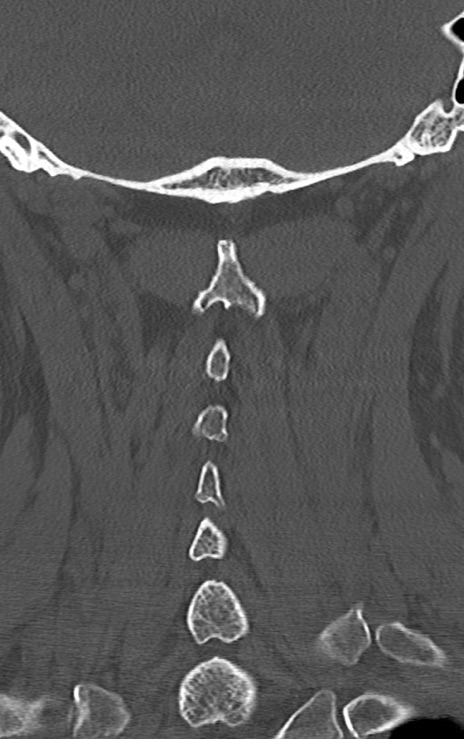

頚椎CT

矢状断像